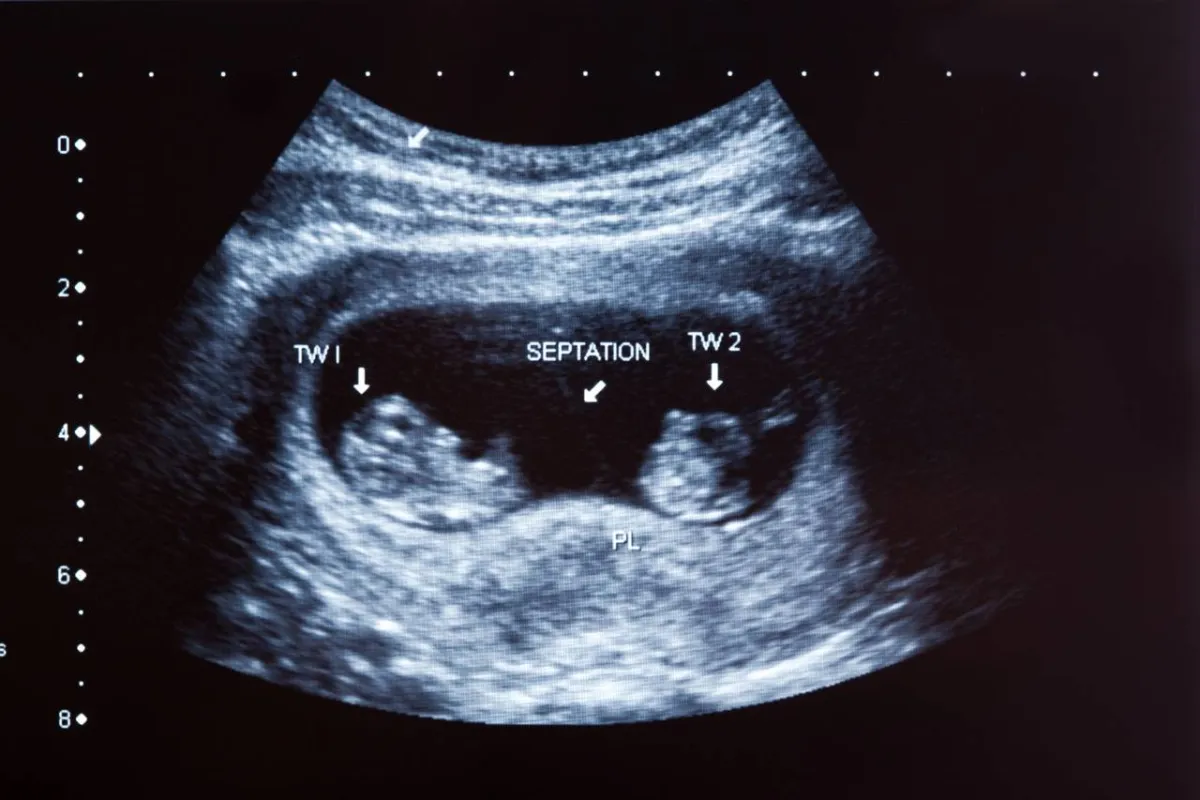

5. تقوم المشيمة بعمل أربعة أعضاء

يُطلق على المشيمة اسم "شجرة الحياة"، فهذا العضو معقد التركيب، ويساعد الطفل على التخلص من الفضلات السيئة، وإمداد دمائه بالكامل وإطعامه، هذه المهمات المتعددة، من فضائل خلق رب العالمين.